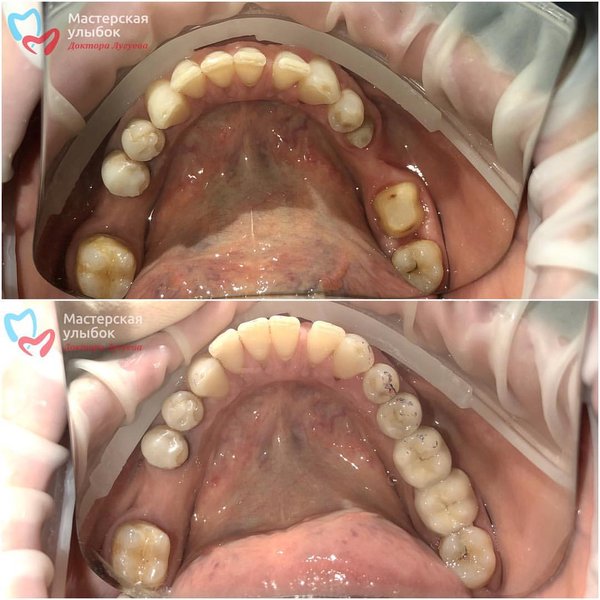

Восстановление анатомической формы зубов и восстановление культи под коронку Работа врача: Аскерхана Мирзахановича